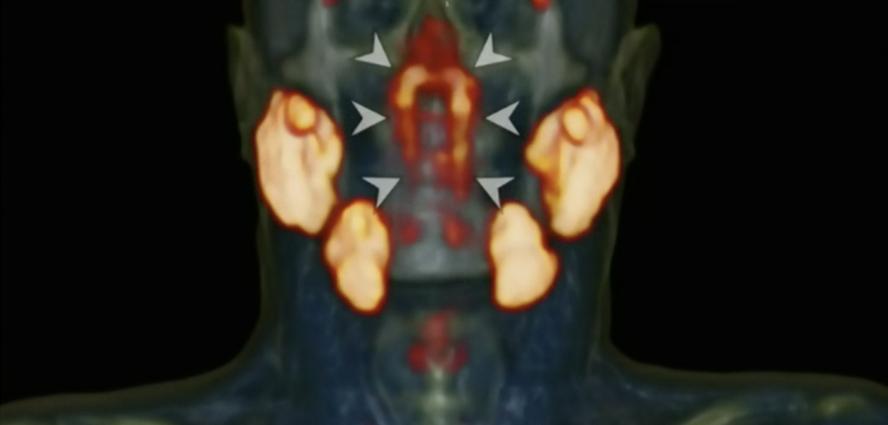

另一项人类进化的证据来自荷兰癌症研究所(NCI)。根据以往的医学记载,人类只有舌下腺、颌下腺和腮腺三个唾液腺,但NCI的研究人员却意外发现了第四套腺体,一个“新器官”——小管腺,位于鼻后喉咙的上部。

图源:荷兰癌症研究所丨《放射治疗与肿瘤学》由此可见,人类没有停止进化的脚步,人们之所以难以察觉,只是因为进化出新特性需要漫长的时间。